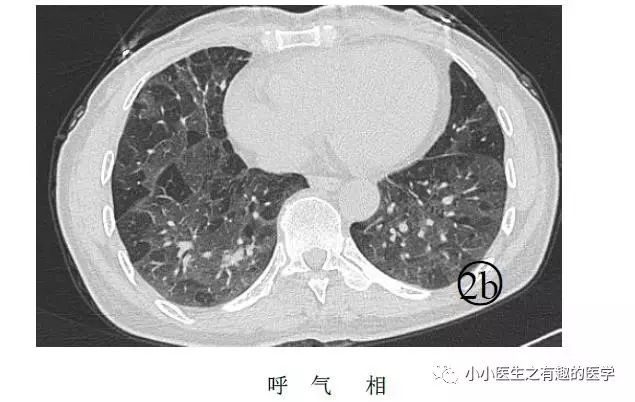

另外,CT发现肺纹理减少,也要警惕肺栓塞。先来说说马赛克。

马赛克征象:由于气道疾病或肺血管性疾病,引起相邻的肺区血液灌注上的差别而出现的不均匀肺密度区,称马赛克灌注。

以图说话,下面都是马赛克,注意了

↓↓↓

如图:

假如CT平扫发现肺部某些地方血管稀疏,灌注不足,千万不要以为没事,有时候,就是肺栓塞,需要警惕。

马赛克,需要警惕肺栓塞,它是肺栓塞的间接表现。并且,在临床中,间断会遇到这样的情况。